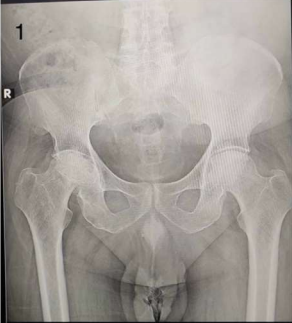

Interestingly, AVN of the hip was more frequently observed on the right side (50%) compared to the left (41.67%) and bilateral presentation (8.33%) among patients with a history of COVID-19. Figures 1 and 2 describe Plain X-rays of pelvis with both hip joints of a 51 year old male and a 43 year old male, having stage 4 AVN of hip, involving the right and left sides respectively. Figures 3 and 4 represent the post-operative X-rays of the above mentioned patients after uncemented THR on the respective sides.

Figure 1: Plain X-ray of pelvis with both hip joints of a 51 year old male having stage 4 AVN of hip, involving the right side.

Figure 1